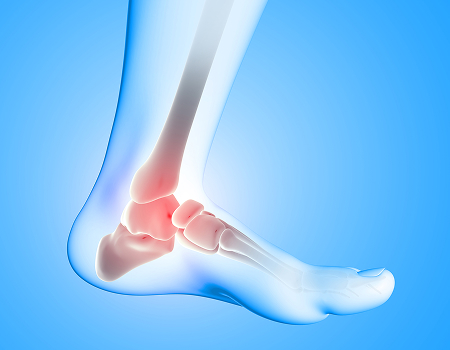

Sport Injuries